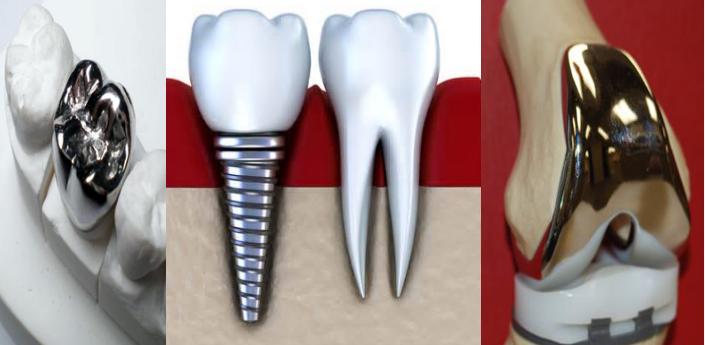

2)什么是人工关节? 人工关节(又称人工假体)是以各种不同生物材料制成的模拟人的关节,如同假牙、心脏瓣膜等一样,也是一种人工器官,而且是目前世界上最成功的人工器官。

3)人工关节的技术原理

人工关节置换技术是使用合金、聚乙烯材料来替换磨损破坏的关节软骨表面,这种合金和聚乙烯材料是非常耐磨,大于90%的病人可以使用超过20年。